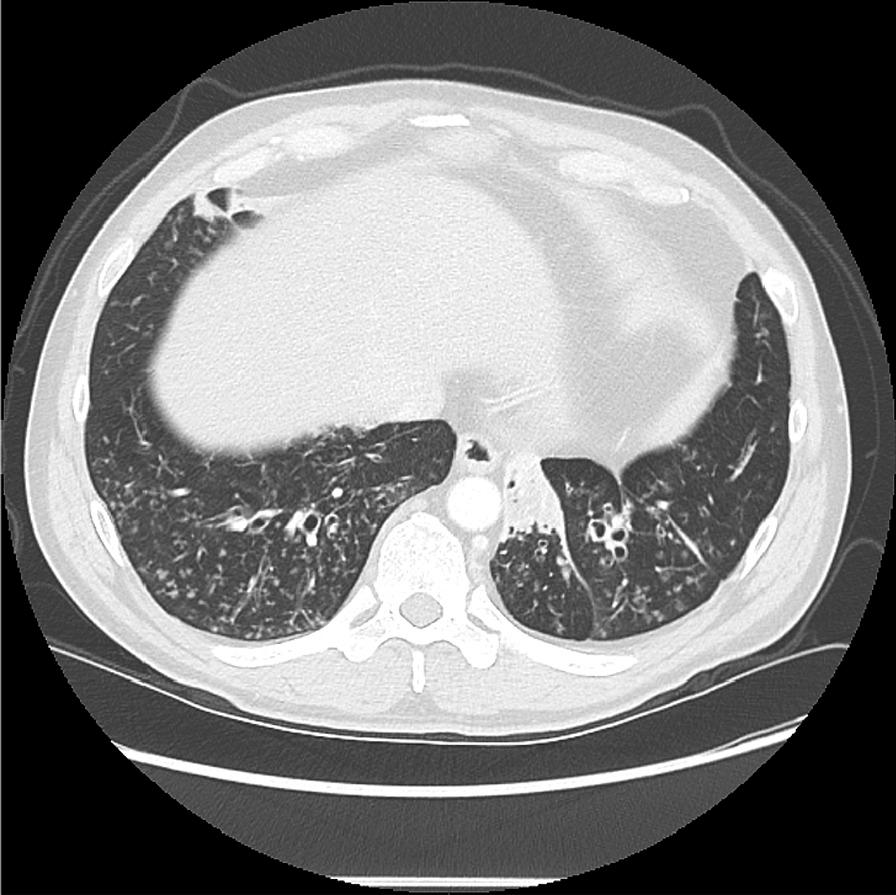

培训网络研讨会对减少支气管扩张症放射学诊断中观察者间变异性的效果。

The effect of a training webinar on decreasing inter-observer variability in making a radiologic diagnosis of bronchiectasis.

Non-cystic fibrosis bronchiectasis is a clinically important disease with an estimated 340,000-522,000 persons living with the disease and 70,000 being diagnosed annually. The radiographic diagnosis remains a pivotal part of recognizing the disease due to its protean clinical manifestations. As physicians are sensitized to this disease, a greater proportion of patients are being diagnosed with mild to moderate bronchiectasis. Despite the established use of CT chest as the main tool for making a radiologic diagnosis of bronchiectasis, the literature supporting the process of making that diagnosis is somewhat sparse. Concurrently, there has been an increased trend to have Web-based radiologic tutorials due to its convenience, the ability of the learner to set the pace of learning and the reduced cost compared to in-person learning. The COVID-19 pandemic has accelerated this trend. We wanted to look carefully at the effect of a Web-based training session on interrater reliability. Agreement was calculated as percentages and kappa and prevalence adjusted kappa calculated. We found that a single Web-based training session had little effect on the variability and accuracy of diagnosis of bronchiectasis. Larger studies are needed in this area with multiple training sessions.

摘要

非囊性纤维化性支气管扩张症是一种具有重要临床意义的疾病,估计有 34 万至 52.2 万人患有该病,每年有 7 万人被诊断出来。由于其临床表现多样,放射诊断仍然是识别该病的关键部分。随着医生对该病的认识提高,越来越多的患者被诊断为轻度至中度支气管扩张症。尽管 CT 胸部检查已被确立为支气管扩张症放射学诊断的主要工具,但支持该诊断过程的文献却有些缺乏。同时,由于其便利性、学习者能够设定学习速度以及与面对面学习相比成本降低,基于网络的放射学教程的趋势有所增加。COVID-19 大流行加速了这一趋势。我们想仔细观察基于网络的培训课程对评分者间可靠性的影响。我们以百分比和kappa 和调整后的kappa 计算来计算一致性。我们发现,单次基于网络的培训课程对支气管扩张症的诊断变异性和准确性几乎没有影响。在这个领域需要进行更多的研究,包括多次培训课程。